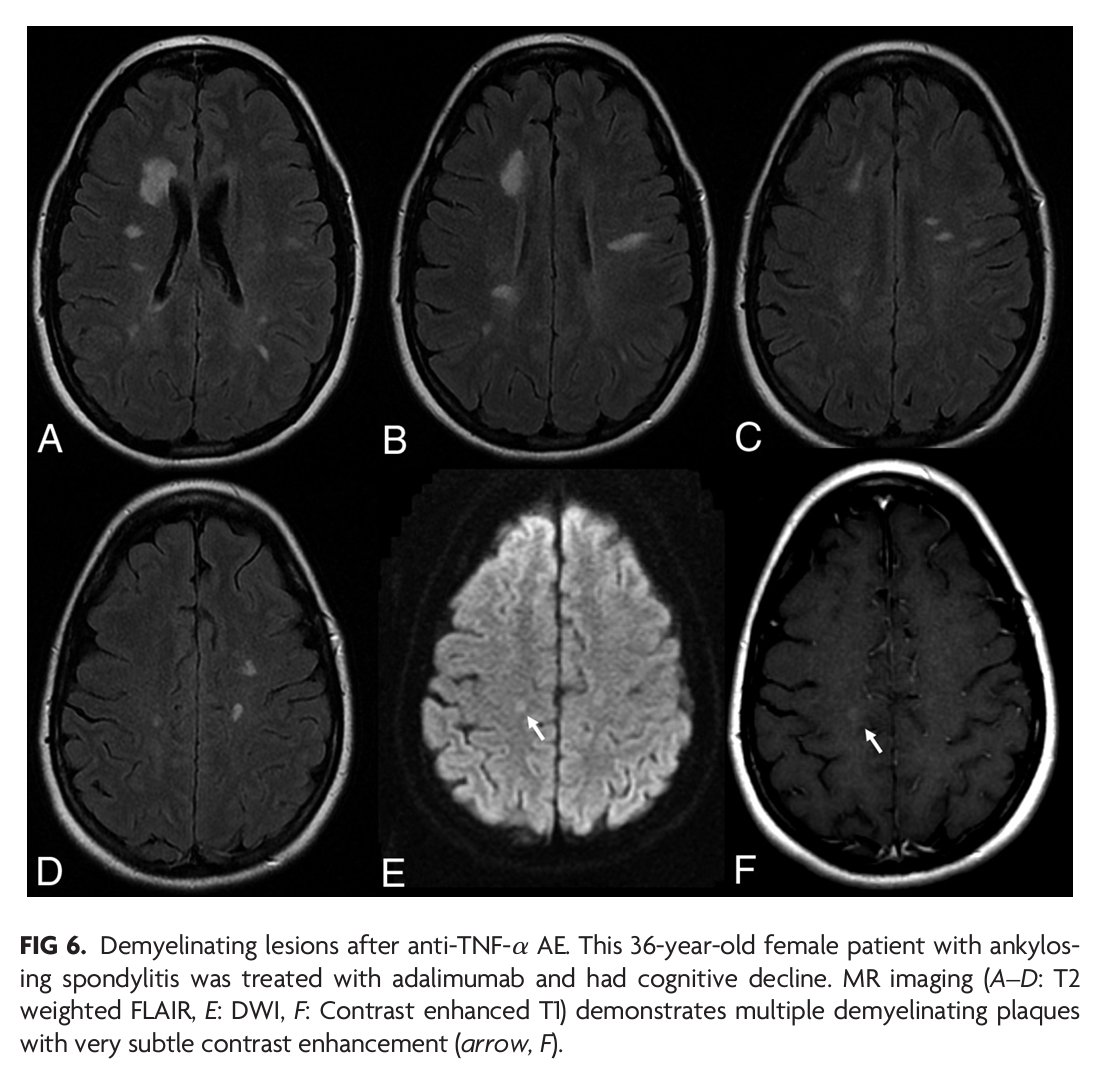

"Monoclonal Antibodies: What the Diagnostic Neuroradiologist Needs to Know" #OpenAccess #ReviewArticle #FellowsJournalClub | bit.ly/3RiHfaN